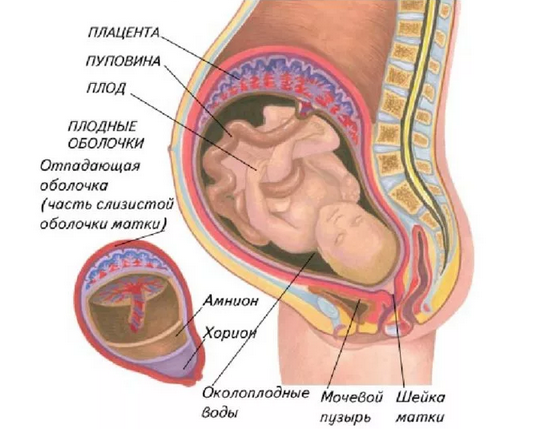

Амнион и Околоплодные Воды: Функции и Роль в Беременности